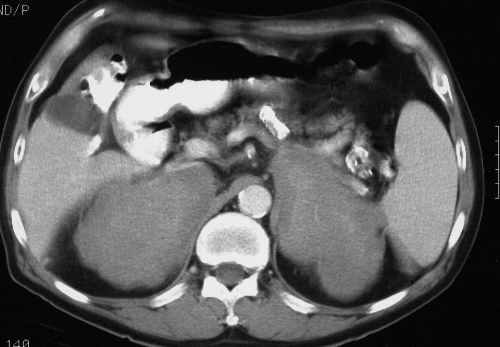

In a patient with a known malignancy, particularly in lung or breast carcinomas, the finding of bilateral adrenal masses most likely represents metastatic disease. However, documenting the entity of metastatic adrenal disease is sometimes a decision focus for the type of treatment a patient may receive. In these circumstances, an adrenal biopsy must be performed .

The finding of bilateral masses (green overlay), in a patient with a known malignancy most likely represents metastatic disease. This patient has known lung carcinoma and bilateral masses with peripheral enhancement, which almost certainly represents metastatic disease. Courtesy of: Ashley Davidoff, M.D. |